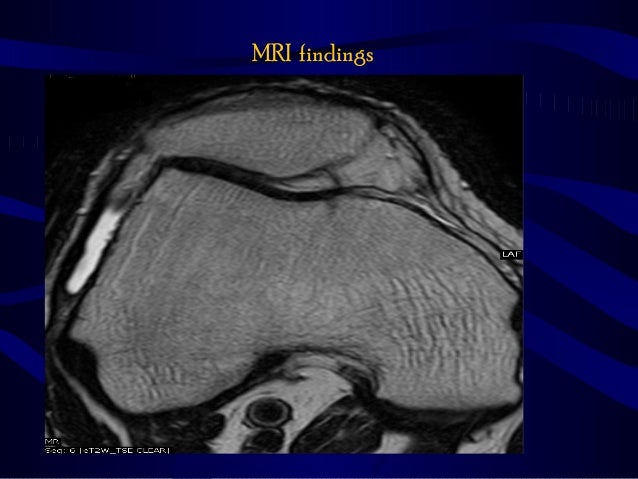

Patients usually present with insidious onset anterior knee pain aggravated by physical activity. MRI shows femoropatellar incongruence with lateral positioning of the patella suggesting lateralizationThis is refered to as excessive lateral pressure syndrome better demonstrated in various femoropatellar articulation X-rays. This may put strain on the medial side and tenderness in the region of the medial patellofemoral ligament MPFL.

Ppt Anterior Knee Pain Powerpoint Presentation Free Download Id 1194597